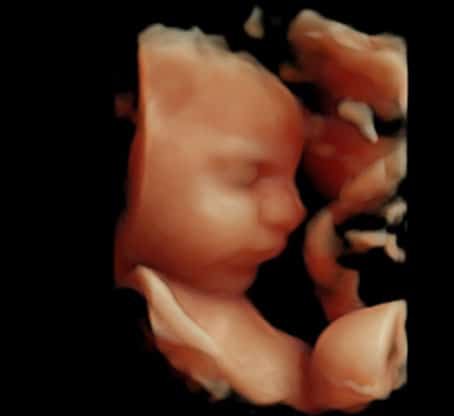

Selon la position du bébé, nous vous proposons une échographie en 3D.